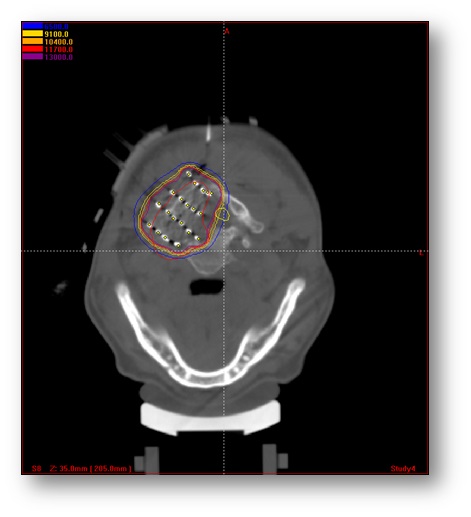

图1 粒子植入治疗椎旁肿瘤病例